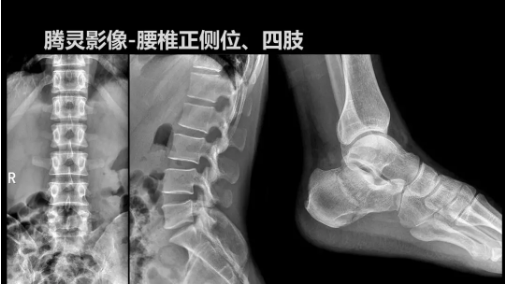

CMEF現(xiàn)場丨安健科技攜動(dòng)態(tài)DR新品“騰靈”亮相展會(huì)

2019年10月19日,82屆秋季CMEF于青島世博城國際展覽中心如期舉辦,國內(nèi)動(dòng)態(tài)DR領(lǐng)域的佼佼者安健科技攜新品——“騰靈”多功能診斷專用動(dòng)態(tài)DR亮相展會(huì)現(xiàn)場。

“騰靈”是安健科技的第四代動(dòng)態(tài)DR產(chǎn)品,可實(shí)現(xiàn)全科室應(yīng)用。如各類常規(guī)的X線檢查、消化道檢查、骨科檢查、婦科、兒科檢查等。此外,安健科技為“騰靈”在真正意義上實(shí)現(xiàn)多科室、多功能診斷進(jìn)行了多項(xiàng)針對(duì)性設(shè)計(jì)。

相較前代產(chǎn)品,“騰靈”在圖像質(zhì)量方面得到了全面升級(jí),“騰靈”采用17*17非晶硅平板探測器設(shè)計(jì),采集矩陣達(dá)3072*3072,動(dòng)態(tài)范圍達(dá)16bit,為成像提供超大視野的同時(shí)保證成像質(zhì)量,此外,該款機(jī)型可根據(jù)醫(yī)療機(jī)構(gòu)的差異化需求而選配不同的動(dòng)態(tài)平板探測器,以此來適應(yīng)不同階層用戶所需。